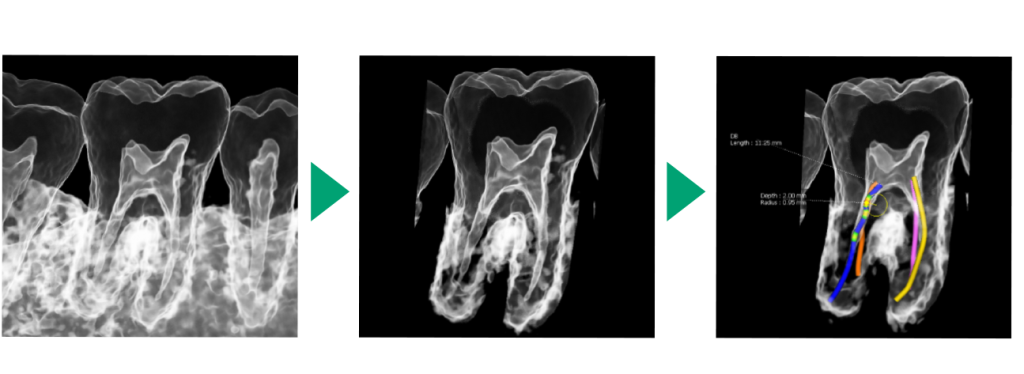

虫歯が大きくて神経をとる治療においては今までのレントゲンでは細かい神経の穴の場所を把握できませんでしたが、CTにより場所を正確に立体化できるため細かい神経の穴の場所を認識しやすくなりました。

インプラント治療において

インプラント治療の成功率が上がる骨の量、骨密度がCTにより正確に把握することができます。

インプラントは骨の中にネジを埋入するものですが、深さ・幅・角度を正確にシミュレーションすることができます。ですので治療の際安全性が格段に向上します。